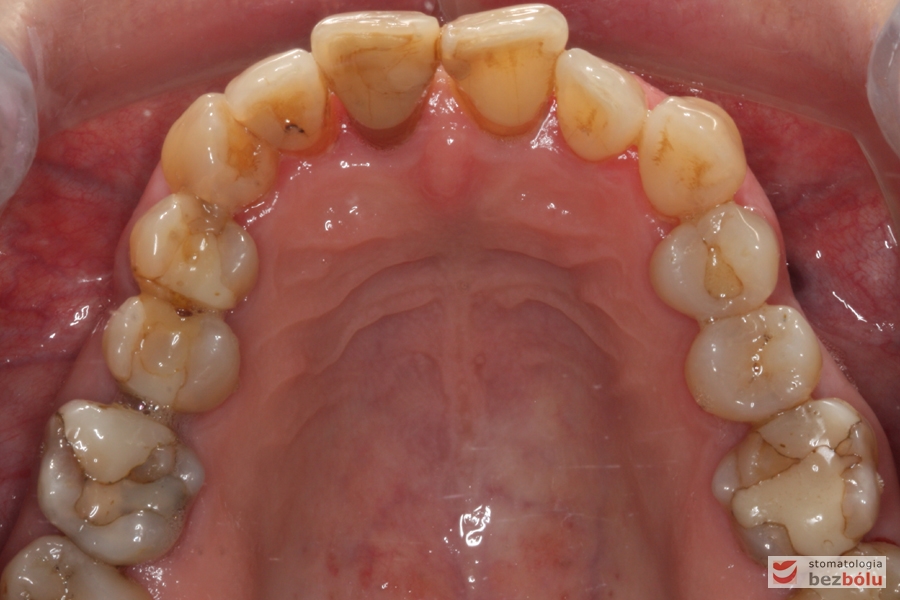

Szczęka - widok powierzchni okluzyjnej, stłoczenia i rotacje w odcinku przednim, zużyte wypełnienia w strefach bocznych

Szczęka – widok powierzchni okluzyjnej, stłoczenia i rotacje w odcinku przednim, zużyte wypełnienia w strefach bocznych